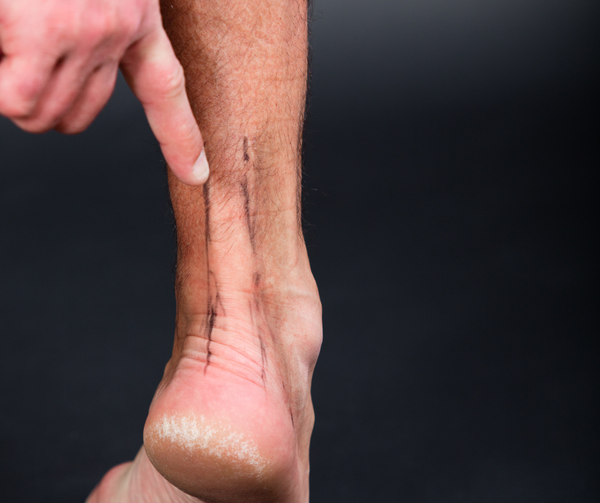

Achilles Tendon PainAchilles Tendon Pain

Achilles tendon pain is a common overuse injury that affects the tendon connecting your calf muscles to your heel. Often caused by repetitive strain, poor footwear, or sudden increases in activity, this condition can lead to stiffness, swelling, and difficulty walking. Early treatment with rest, proper support, and professional care can prevent chronic damage and get you back on your feet.